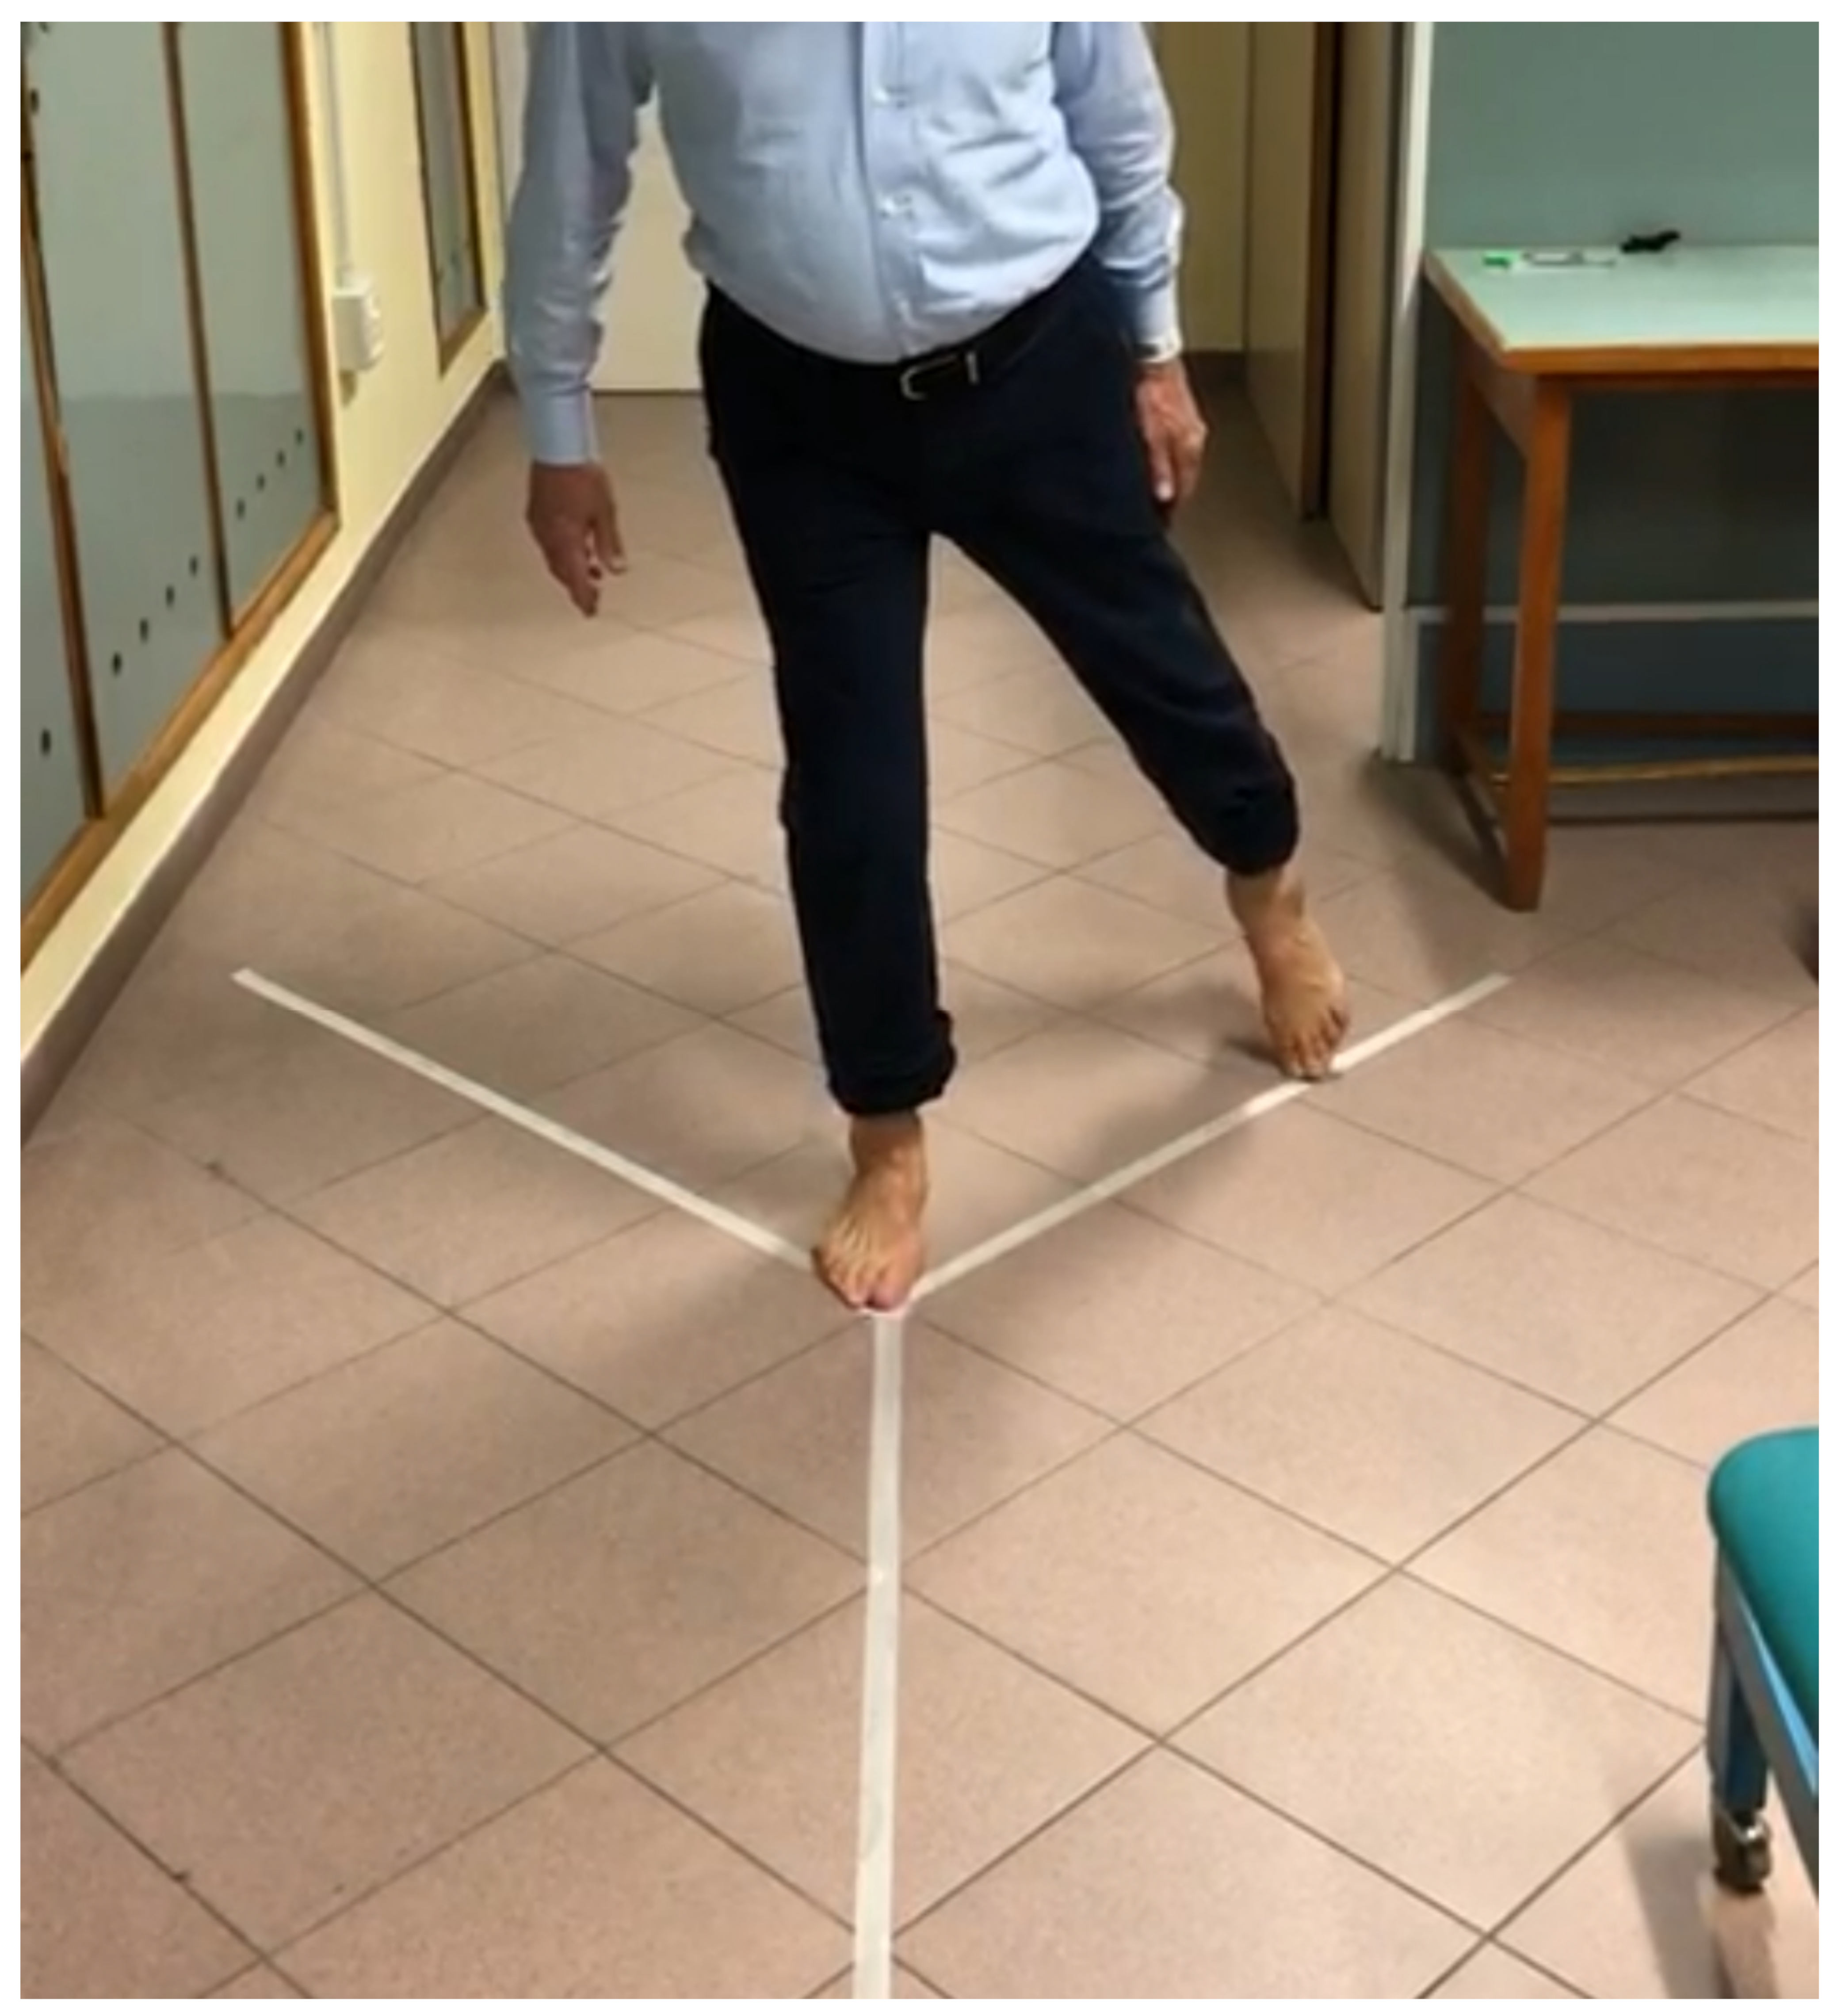

2.4. Data Collection and Measures